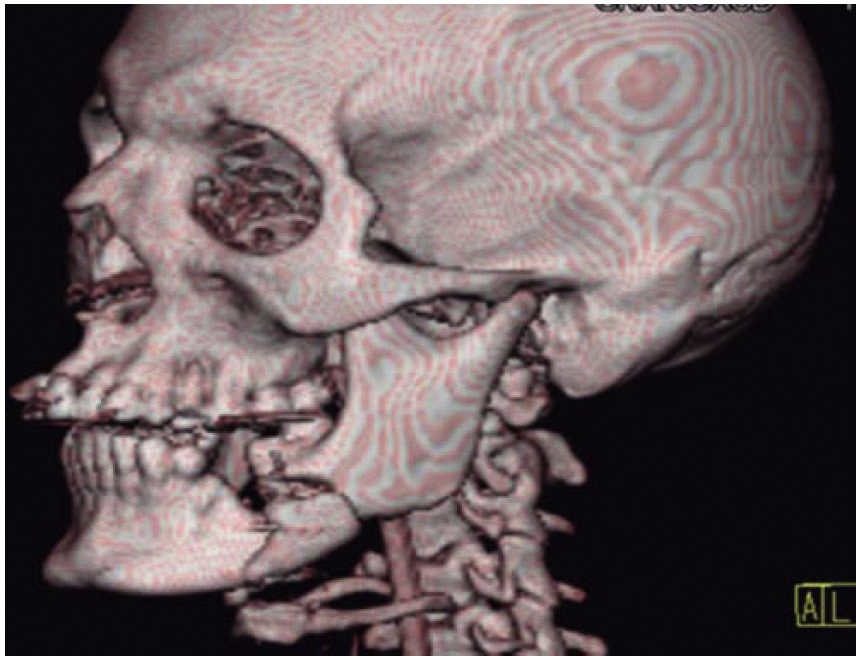

Clinical exploration and vital signs analysis provide a panorama of real bleeding and accumulated blood loss (Step B). Once the airway has been stabilized and the hemodynamic status is confirmed, proper ventilation of the patient must be secured with appropriate measures (Step C). In cases of active bleeding, first treatment is local pressure application with tamponade (plugging). If there is no improvement in hemodynamic situation, an angiography is performed, and as specific measure, an intervening image expert performs an embolism or surgical exploration and injured vessel ligation.13 Once the patient is stabilized, area specialists will assess presence of intracranial, thoracic, abdominal, orthopedic and ocular trauma.7 Pharmacological treatment initiates with, among others, administration of solutions, blood derivatives, antibiotics, analgesics, and anti-tetanic prophylaxis.14 Once urgent treatment has been provided by the aforementioned specialists, comprehensive assessment of firearm lesions in the maxillofacial region is undertaken. Manson uses four components for this evaluation: soft tissue damage, bone alteration, soft tissue loss and bone loss.15 The wound is cleansed with physiological solution; contaminant material, necrotic tissue and foreign bodies are removed. The projectile's entry and exit orifices are identified, as well as lesions caused in the course of trajectory. In cases when no exit orifice is found, it must be established in which space or tissue might the projectile be lodged.16 Bone damage assessment is initiated with palpation, and it is supported with simple image studies such as orthopantomography and Waters’ X-ray; in order to design treatment plan the aforementioned can be supplemented with a computerized tomography with 3-D reconstruction.12,17

Clinical case 3

A 73 year old female with diagnosis of fracture of left mandibular body due to firearm projectile (Figure 12). The patient informed she was assaulted in the street, and upon offering resistance to the theft of her vehicle, she was shot at a distance of two meters. She arrived at our institution eigt days after the assault, having previously been treated in another hospital. Physical exploration revealed hyperemic area and volume increase in fluctuating left submandibular region; entry orifice at left submandibular level with presence of fetid whitish secretion and closed exit wound at right cervical level. Intraoral examination revealed partial edentulism, with multiple maxillary septic foci, and at the left mandibular fornix, a root remnant of the first molar in the fracture line as well as accentuated mobility of the mandibular segment caused by fracture which hindered deglutition.

Treatment was initiated with immunization, antibiotic therapy, analgesia, extraction of septic foci and mechanical cleansing of the wound. The patient lacked removable or partial prostheses, so in order to establish inter-maxillary relationship and facial height, gunning splints were manufactured in order to establish inter-maxillary relationship (Figure 13). After ten days of initial treatment, the patient exhibited suitable alveolar healing, with presence of non-fetid secretion at the level of the mandibular wound. The second procedure was then undertaken with extra-oral approach; a 2.4 mandibular reconstruction plate and a 2.0 bone segment plate were used (Figures 14 and 15). The patient was discharged, and she attended periodic assessment visits which showed suitable healing (Figure 16) and adequate mandibular mobility. Three weeks after reconstruction, the patient was instructed to initiate prosthetic treatment in order to achieve rehabilitation.